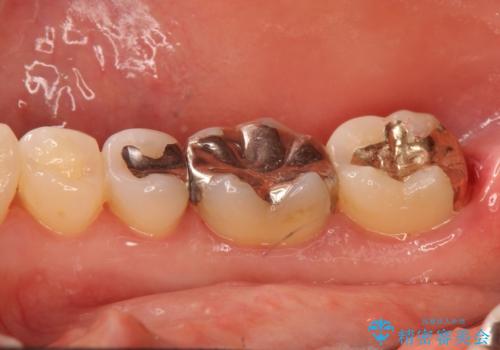

- 詰め物が外れたから作り直しをしたいとのことで来院されました。

外れた状態で日にちが経過していたため、まわりの歯ぐきが歯の上に乗っかっている状態です。

歯ぐきの形を整えてから治療をしていきます。